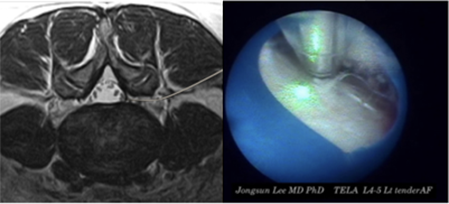

윤성훈 과장신경외과

요통, 경추통, 방사통, 척추 골절, 척추 디스크, 척추관협착증, 척추전방전위증, 신경차단술, 척추신경성형술, 디스크고주파 감압술, 양방향 / 단일공 내시경하 수핵제거술, 척추 풍선복원술, 경추/요추 퇴행성질환 교정술 등